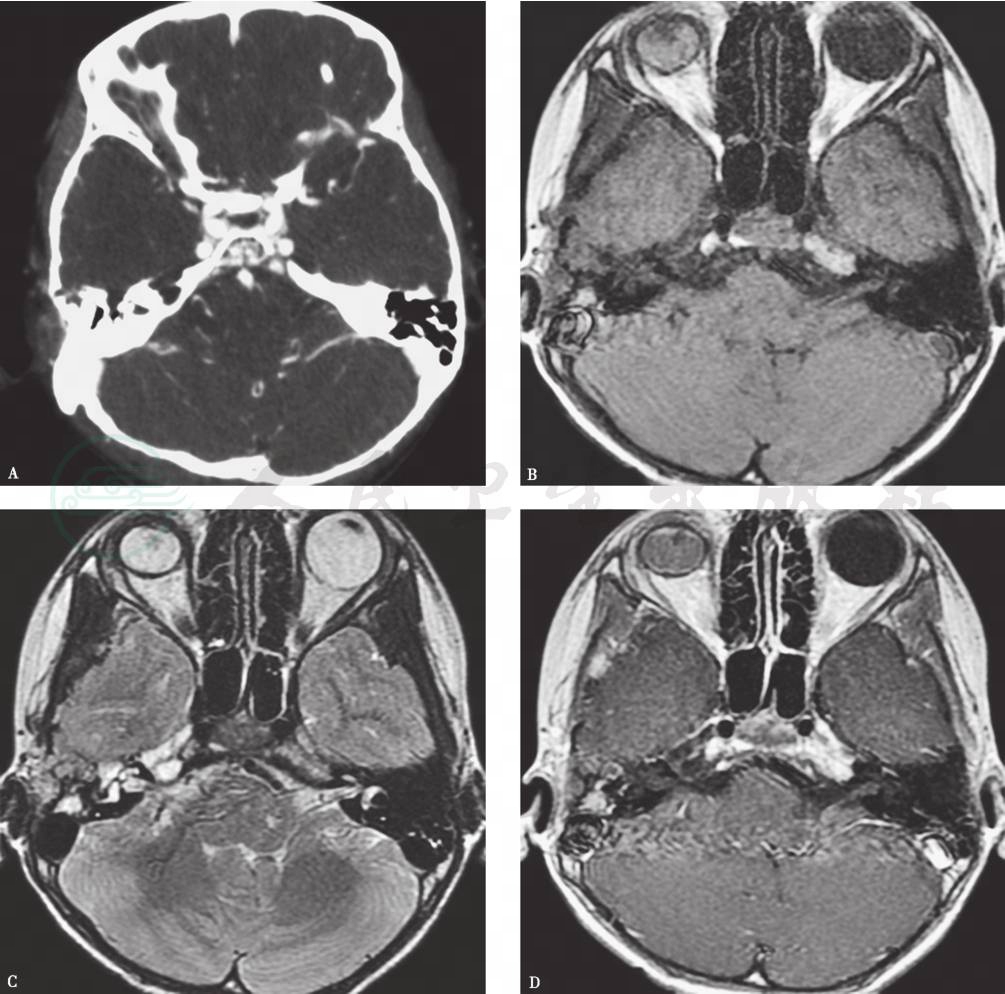

根据发病部位不同,其表现各不相同:①当肿瘤位于鼓室内时,主要表现为鼓室内不规则形软组织肿块,其内可见钙化;②当肿瘤位于内耳道壁或岩尖骨质时,骨质膨大呈蜂窝状或珊瑚状结构,并有骨质破坏,其边缘不整齐;③当肿瘤位于面神经管时,可见前膝部或迷路段骨管扩大,骨质破坏,边缘较毛糙(图1A)。

2.MRI表现

肿瘤在T1WI上呈等信号,T2WI上呈高信号,增强后扫描明显强化(图1B~D)。

图1血管瘤

A.颞骨增强HRCT横断面,示右侧颞骨鳞部、岩部交界处斑片状强化软组织影;B~D.颞骨横断面T1WI、T2WI、增强T1WI,显示鳞部、岩部交界处斑片状稍长T1稍长T2信号影,增强后轻度强化;病变后部见小片状较短T1长T2信号区,增强后明显强化